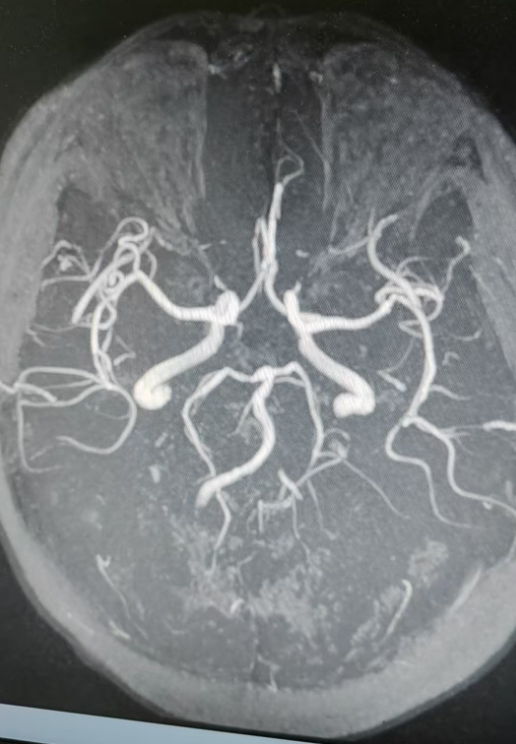

经颅多普勒超声及颅脑MR平扫+DWI+MRA检查显示:颅骨及颅外软组织未见异常,脑灰白质分布正常;两侧侧脑室旁、基底节、左侧丘脑、脑桥可见斑点状、小片状异常信号,部分区域伴脑软化及周围胶质增生;两侧额顶叶、侧脑室旁白质存在脑白质脱髓鞘改变,并伴有增龄性脑萎缩;同时提示部分空泡蝶鞍,两侧上颌窦、筛窦粘膜增厚;脑血管方面,存在脑动脉硬化,左侧大脑中动脉M2段、大脑后动脉P3段等多部位血管局部变窄,基底动脉远端局部开窗,左侧椎动脉未显示。结合检查结果与病史,患者转入内二科(神经内科·肾病)进一步救治。

正是这次检查,发现他:1.左侧椎动脉狭窄;2.不完全性偏瘫3.多发腔隙性脑梗死4.高血压病3级(很高危)5.2型糖尿病伴周围血管病。

术中,医护团队精准操作,顺利完成全脑血管造影右侧椎动脉V4段球麻醉方式囊扩张+支架植入等关键步骤。手术顺利,患者安返病房,医护团队密切监测其病情变化,给予针对性护理及对症治疗。

术后,复查双侧椎动脉造影显示,血管鞘在股动脉内位置良好,缓慢拔出血管鞘,Starclose闭合器闭合股动脉满意,病变血管已成功“疏通”。